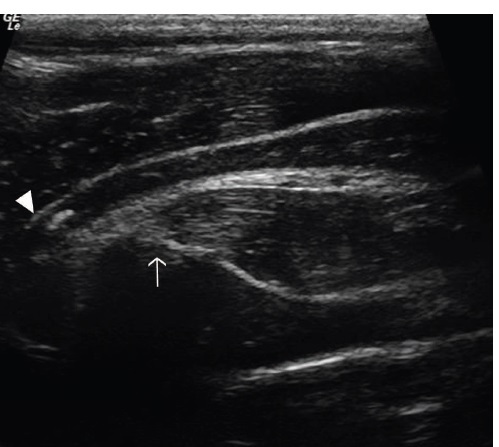

FIGURE 15 Caudoventral window – transverse plane: A, The left Plica vocalis at 6-12 months postsurgery. Plica vocalis base (white arrow) is

hyperechoic compared to the right Plica vocalis. This is consistent with thickening of the tissue in this area, attributed to a granuloma. There is a

luminal ringdown artifact created by this mass. Right to the left of image and the skin/ventral at the top. B, The corresponding right Plica vocalis at

6-12 months postsurgery on endoscopy. The Plica vocalis granuloma can be clearly seen (white arrow). Right to the left of the image [Color figure

can be viewed at wileyonlinelibrary.com]